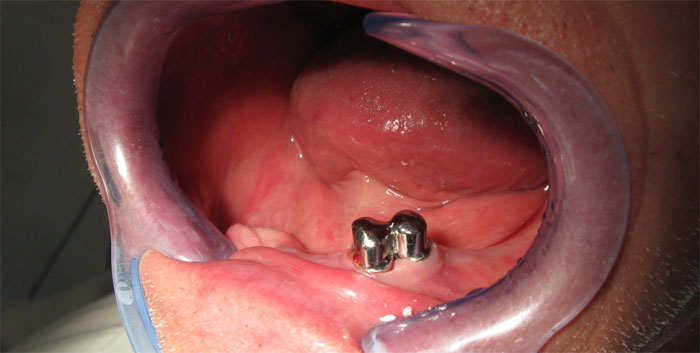

Unterkiefer

Im Februar wurden die Zähne 43 und 44 gezogen (links auf dem Röntgenbild), am selben Tag wurde eine vorläufige metallfreie Kunststoffprothese der Marke DEFLEX gefertigt. Ende Mai 2012 wurde eine herausnehmbare IVOCLAR-Stegprothese auf zwei Teleskopkronen gesetzt.